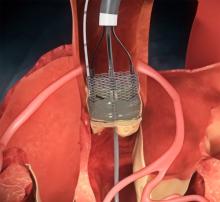

The Boston Scientific Corp. Lotus Valve System met a performance measure in the treatment of symptomatic patients with severe aortic valve stenosis considered at high risk for surgical valve replacement, according to new data released at the 25th annual Transcatheter Cardiovascular Therapeutics scientific symposium (TCT 2013) in San Francisco.